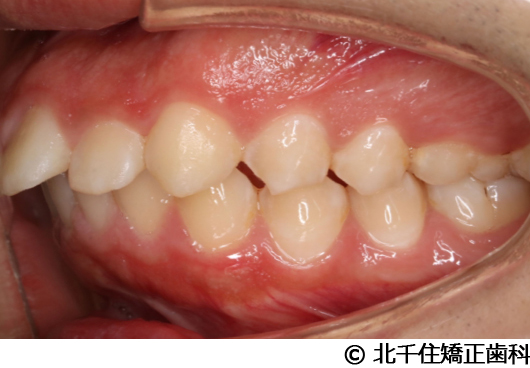

【症例2】上顎前突症

- 治療前

- 治療中

- 治療後

主訴:出っ歯、口元の突出、横顔をきれいにしたい

治療方法

骨格性の上顎前突、上下顎第一小臼歯4本及び上顎第二大臼歯を抜歯して矯正用アンカースクリューを併用してワイヤー矯正治療(セラミックブラケット)。

治療結果

骨格性上顎前突に対し、抜歯および矯正用アンカースクリューを併用した矯正治療により歯列および咬合関係の調整を行った症例である。治療後は保定装置を使用し、歯列および咬合の安定維持を目的として定期的な経過観察を行っている。